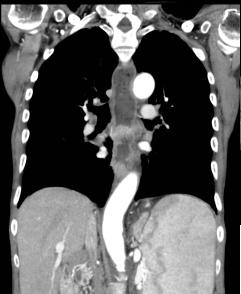

Un autre cas de cancer epidermoide du

1/3 moyen de oesophage avec metastase ganglionaire

pulmonaire . Bilan pre-therapeutique .

- Image TDM fenetre mediastinal en coupe

coronal ( frontale) et en coupe axiale a

traverse la tumeur . Image du tumeur de

oesophage avec extention locaux aortique et au

ganglions pulmonaires